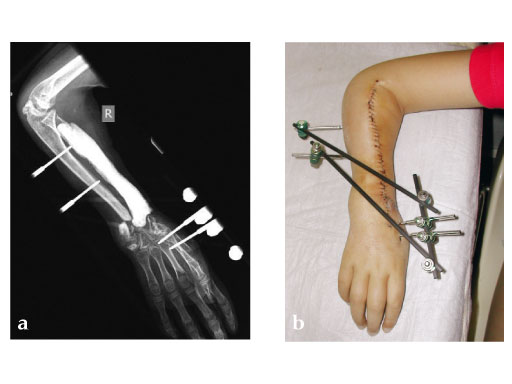

Fig 2ab: Resection of necrotic radius, temporary ExFix and pallacos spacer.

Fig 3a: Microvascular osteocutaneous free fibula flap for reconstruction of radius and dorsal skin.

Fig 3b: Proximal osteosynthesis with two screws and arthrodesis of wrist wrist with LCP 2.7.